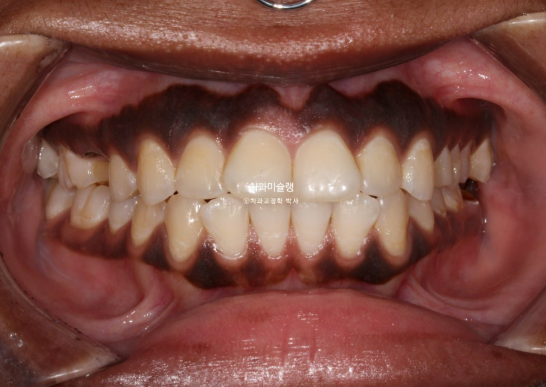

This patient is a foreign individual in their 20s who first visited us in July 2023 for orthodontic treatment.

The patient had previously undergone non-extraction orthodontic treatment but did not wear retainers, resulting in relapse of the anterior teeth. Due to dental caries, several teeth were subsequently lost, leading the patient to seek re-treatment.

In the maxilla, one premolar had decayed to the point where only the root remained.

In the mandible, a molar was in a similar condition, with only the root remaining.